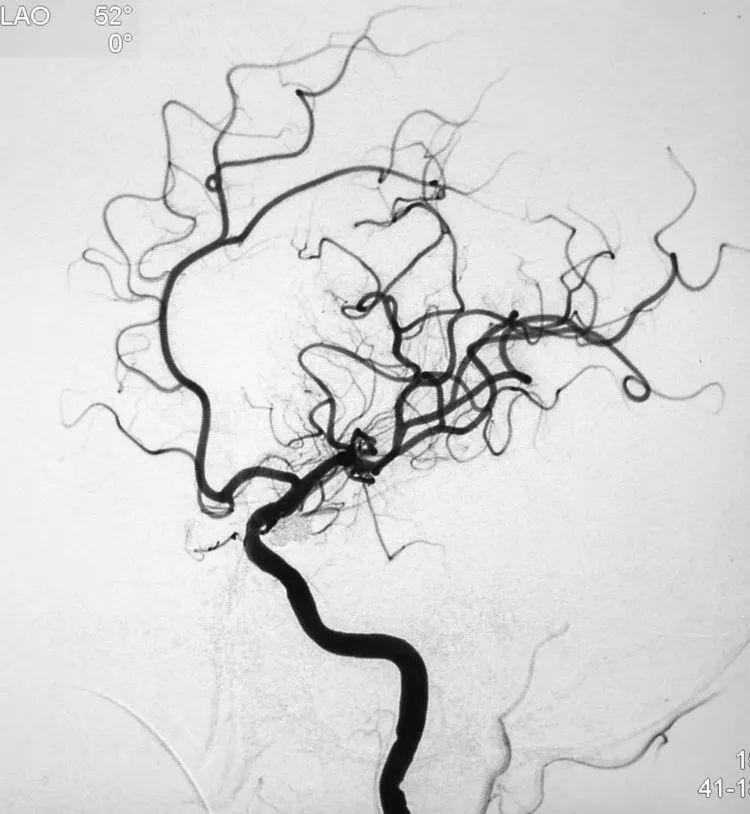

计划支架结合双微导管技术栓塞。6F Navien中间导管在6F长鞘支撑下抵达左颈内动脉破裂孔段。左颈内动脉工作位(LAO 52°)路图下,经Navien送入三套微导管,Headway-21支架导管进入左大脑中动脉;第一根Echelon-10微导管(甲管,头端塑成C形)在Synchro-14微导丝引导下进入大分叶;第二根Echelon-10微导管(乙管,头端塑成猪尾形)进入小分叶: